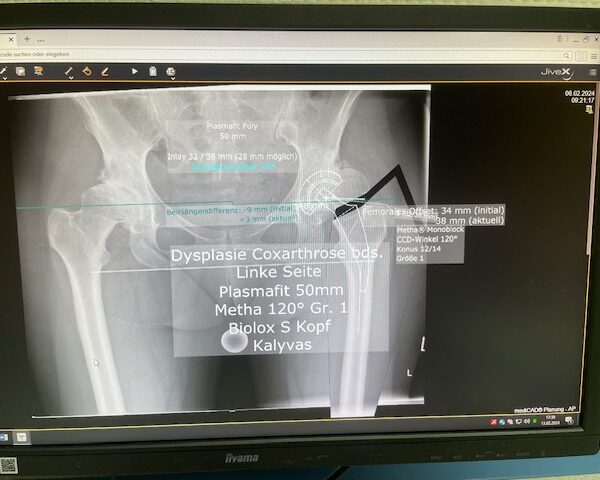

Ο προεγχειρητικός ψηφιακός σχεδιασμός ήταν ιδιαίτερα μεθοδικός και συγκεκριμένος. Η ακτινογραφία λεκάνης της ασθενούς εισήχθη σε ειδικό λογισμικό στον υπολογιστή, το οποίο επέτρεψε τον ακριβή προγραμματισμό της καινούριας θέσης της άρθρωσης.

Μέσω του ψηφιακού αυτού σχεδιασμού, υπολογίστηκε με ακρίβεια το μέγεθος και ο τύπος των προθέσεων, η γωνία του κώνου, καθώς και η σωστή ανατομική τοποθέτηση των μοσχευμάτων. ώστε να επιτευχθεί τέλειος ισοσκελισμός των κάτω άκρων και να αποφευχθεί οποιαδήποτε διαφορά μήκους μετεγχειρητικά!!!

Πρόκειται για ένα εξαιρετικά σημαντικό στάδιο, καθώς εξασφαλίζει τη μέγιστη δυνατή ακρίβεια, ταχύτητα και αποτελεσματικότητα κατά τη διάρκεια της επέμβασης. Επιπλέον, συμβάλλει στην άριστη λειτουργικότητα του ισχίου καθώς και να επιτευχθεί τέλειος ισοσκελισμός των κάτω άκρων και να αποφευχθεί οποιαδήποτε διαφορά μήκους μετεγχειρητικά!!!

Ο προεγχειρητικός ψηφιακός σχεδιασμός αποτελεί πάντα πλήρως εξατομικευμένο πλάνο, προσαρμοσμένο στα ανατομικά χαρακτηριστικά και τις ανάγκες του κάθε ασθενούς, και είναι καθοριστικός για την επιτυχία της επέμβασης !!!